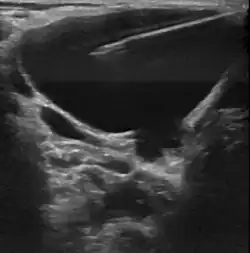

Пороки развития лимфатических сосудов в области головы и шеи чаще всего определяются при рождении или в первые годы жизни ребёнка, в возрасте до одного года в 60-80 % случаев[6]. Основными методами визуализации лимфатической мальформации являются ультразвуковое исследование (УЗИ) и магнитно-резонансная томография (МРТ). Данные исследования позволяют определить площадь и объём патологических тканей, размеры кист, топографию образования.

В настоящее время лимфатическую мальформацию можно визуализировать у плода с конца первого — начала второго триместра беременности. Лучше всего определяются крупно кистозные формы мальформаций. Чаще всего лимфатические мальформации выявляются в области шеи, грудной клетки, языка, туловища и конечностей.[14][15]

• Склеротерапия (склерозирование). Процедура включает в себя аспирацию содержимого кисты с последующей инъекцией склерозирующего агента, который вызывает рубцевание прилежащих стенок кисты. Склеротерапию проводят под ультразвуковой навигацией или с использование ЭОП’а. Склеротерапия не удаляет лимфатическую мальформацию, но она эффективно уменьшает объём поражения. Склеротерапия является методом выбора для лечения больших или проблемных крупно кистозных или смешанных лимфатических мальформациях[21].